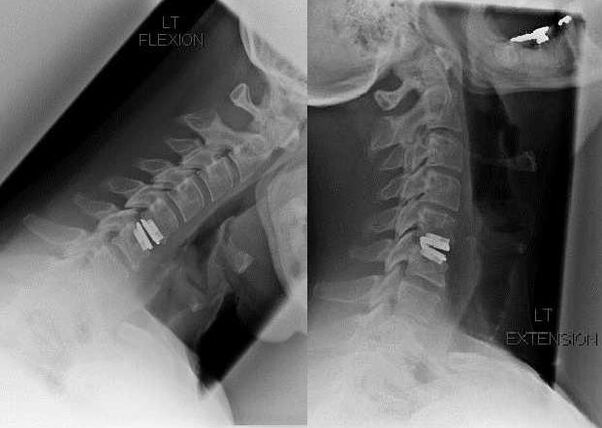

Surgical intervention

Indications for surgical intervention include the ineffectiveness of conservative treatment, as well as complications of cervical spondylosis, for example, discogenic myelopathy, vertebral artery syndrome and nerve root syndrome.To decompress the spinal cord, blood vessels and spinal roots, the following manipulations are performed:

During surgery, pieces of bone and ligaments may be removed, and the disc may be completely or partially removed.For small hernias, laser vaporization of the nucleus pulposus is often performed.

After resection of vertebral structures, stabilization of the spinal motion segments is often required by spinal fusion or installation of autologous bone and skin grafts.